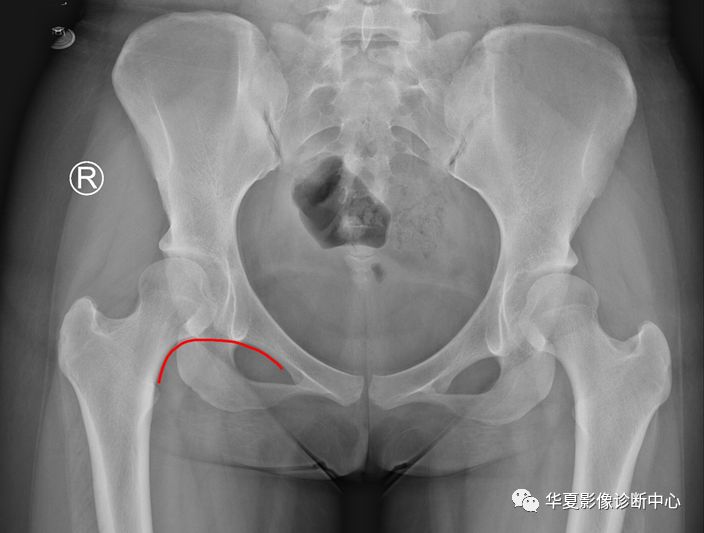

3、Shenton线(耻颈线):髋关节正位片上,闭孔上缘与股骨颈内下缘连线。

正常应为平滑曲线,若不连续提示髋关节脱位或者股骨颈错位骨折。 医学百科网 | YxBaike.Com